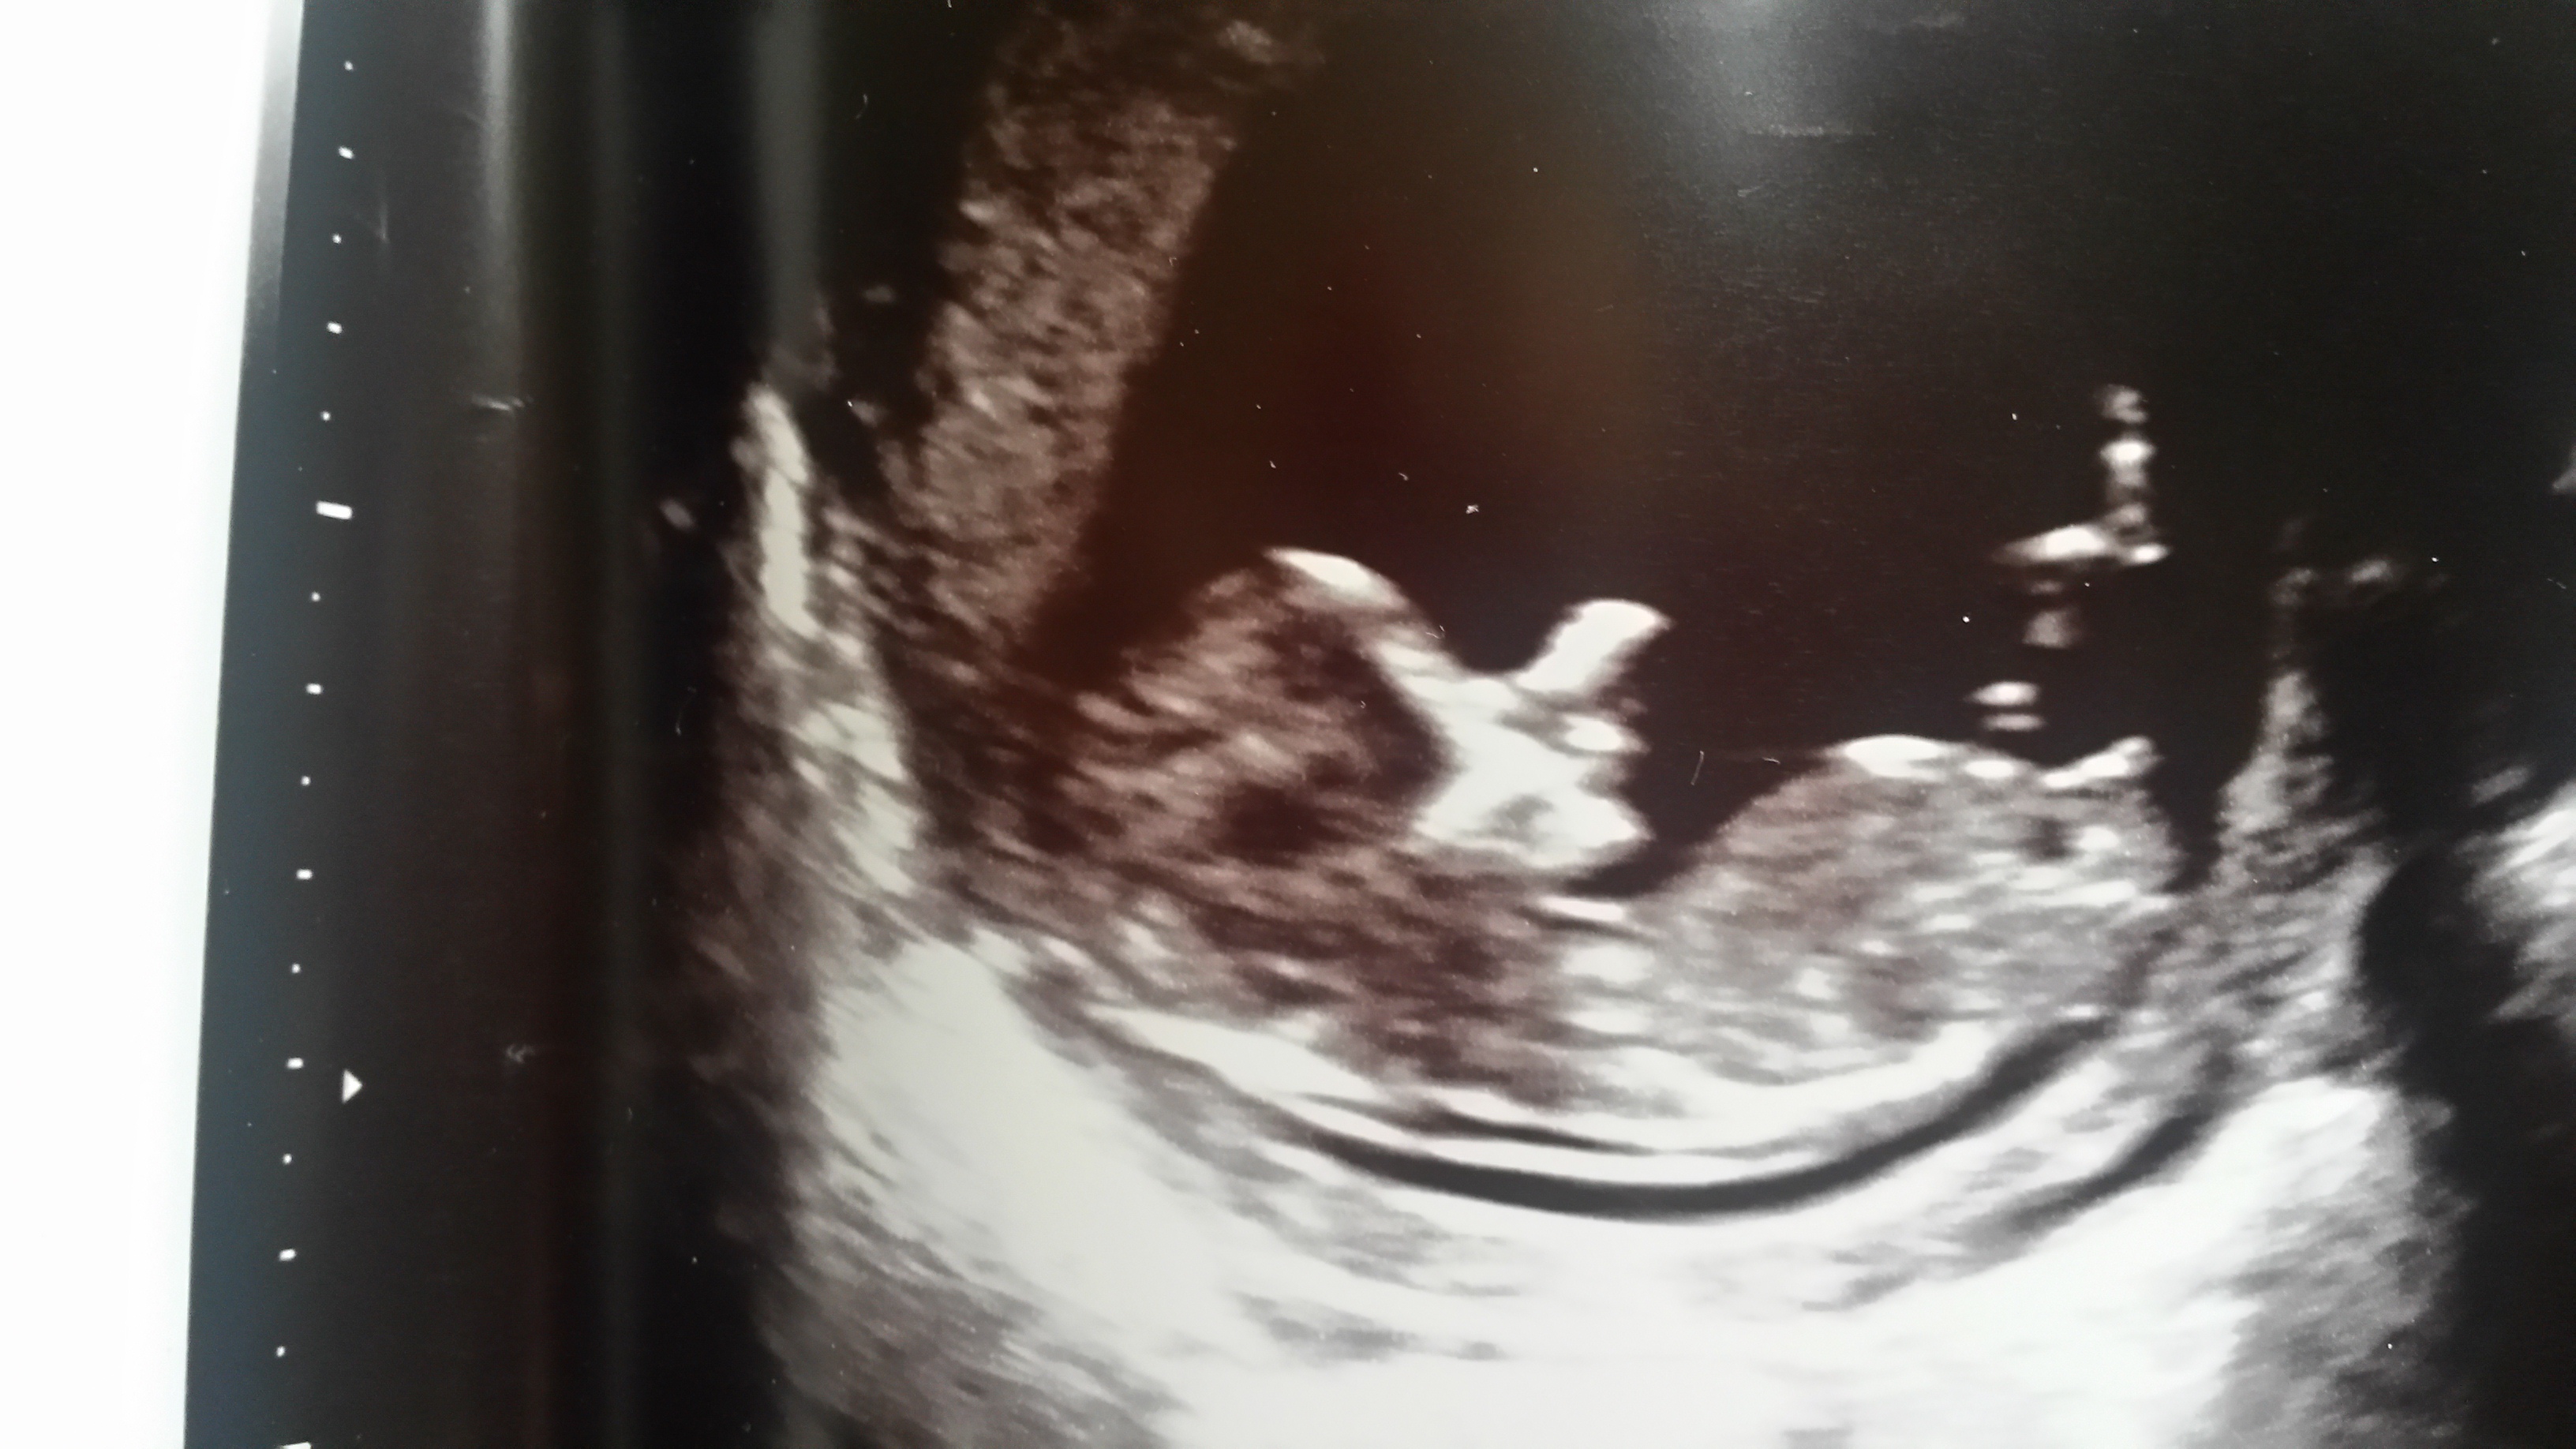

Any guesses? 12 w 4 days